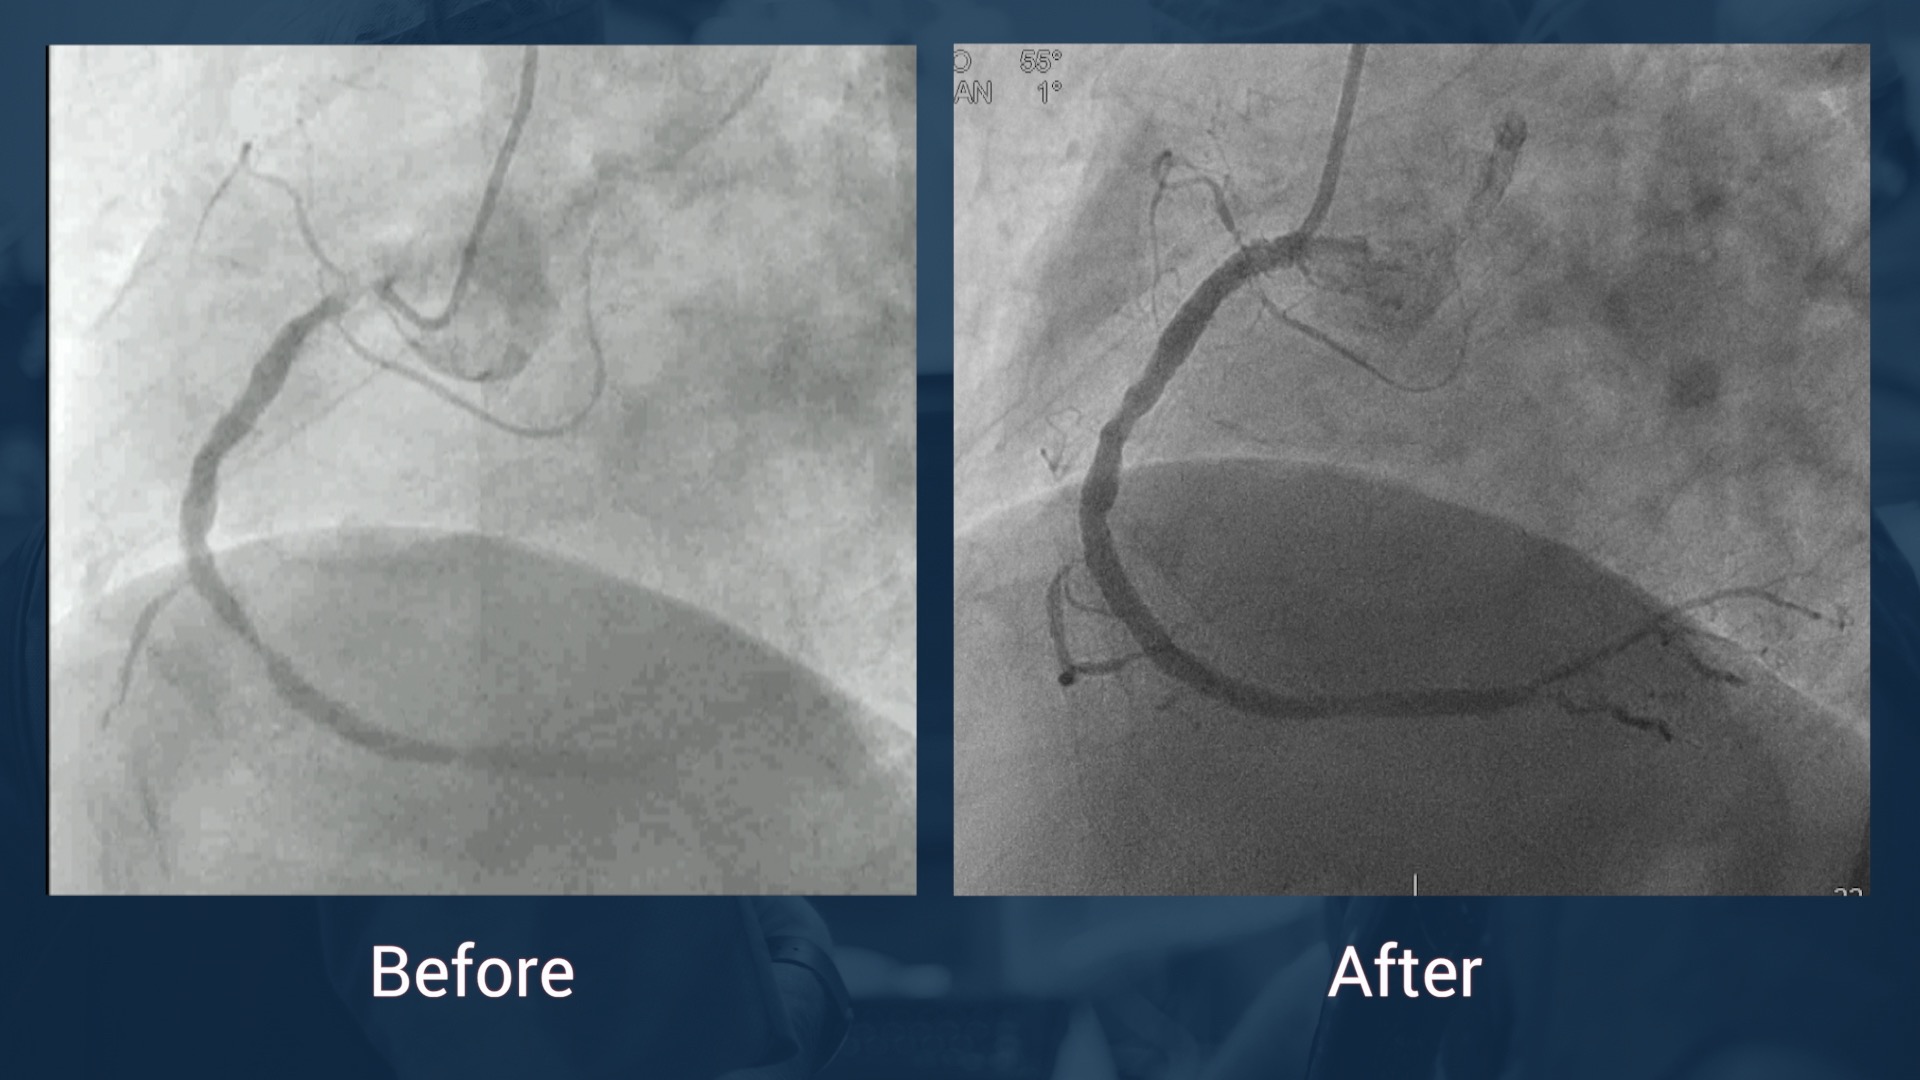

CAG 14.7.17: LAD without stenosis, CX without stenosis, in-stent reocclusion of the RCA

J-CTO score: 1